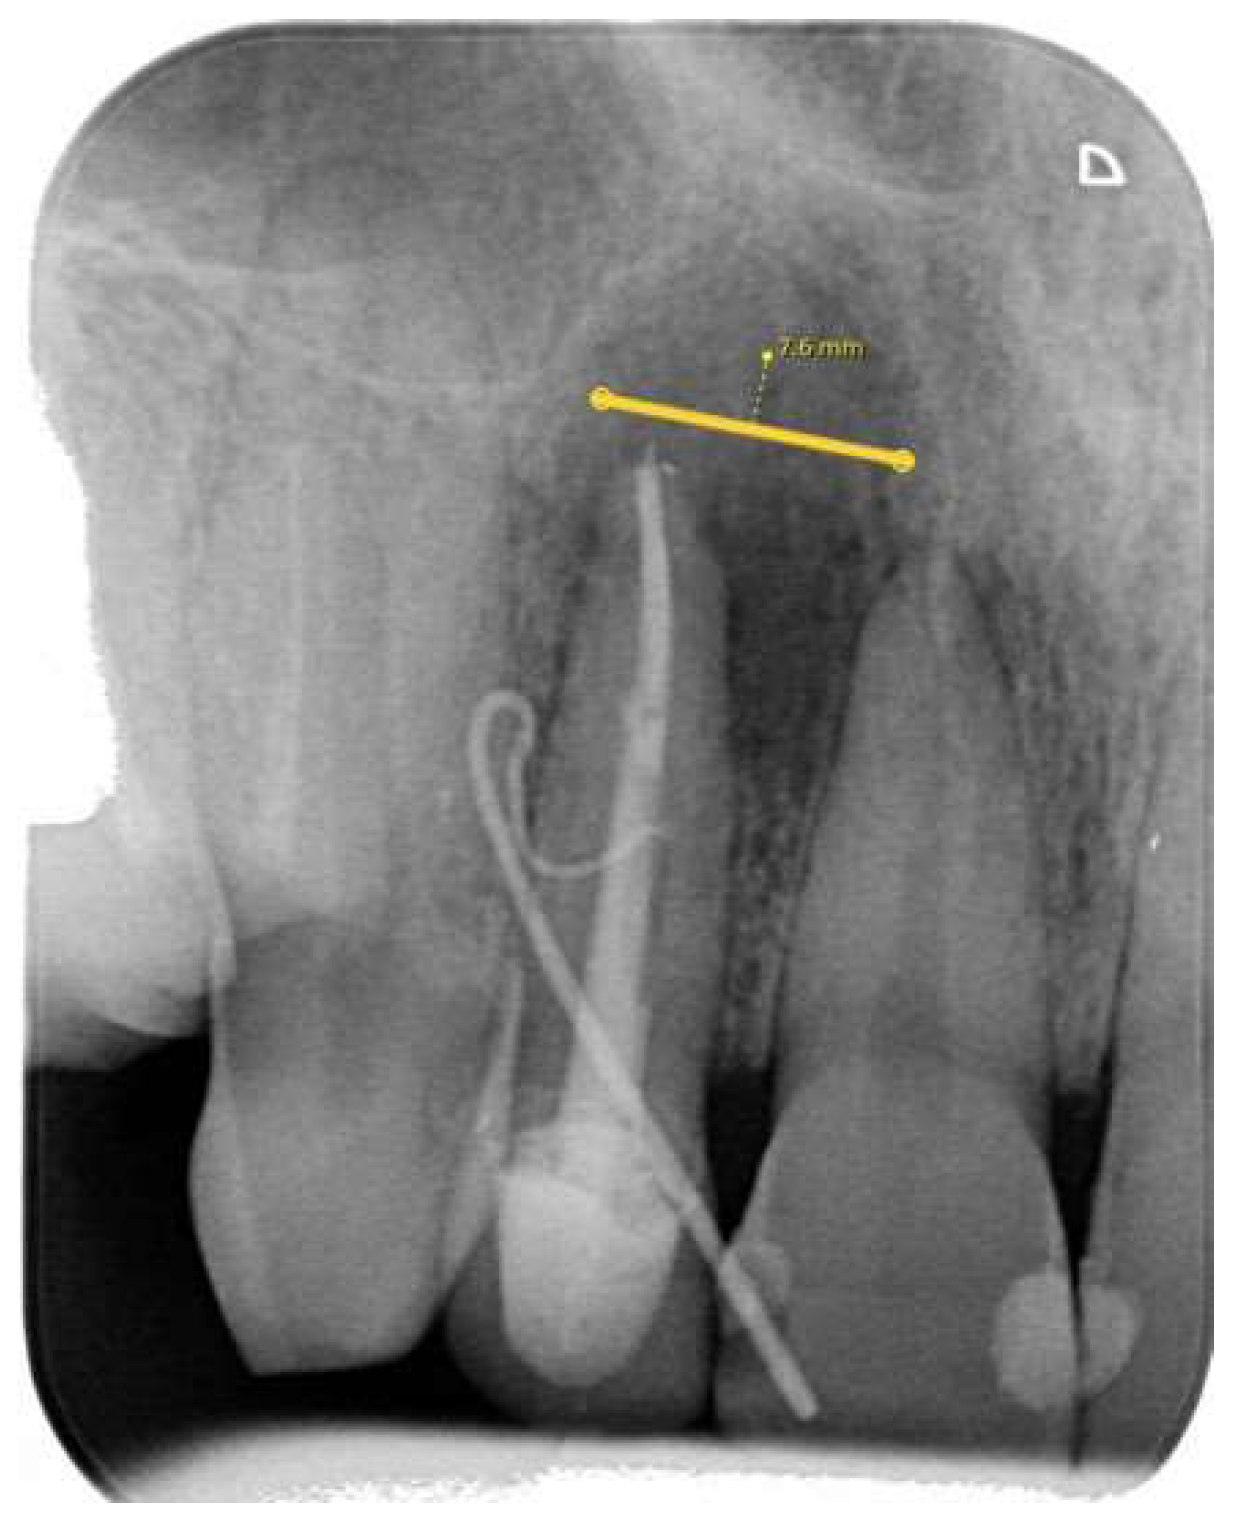

2.3.1. Periapical (PA) Radiography Examination and Evaluation